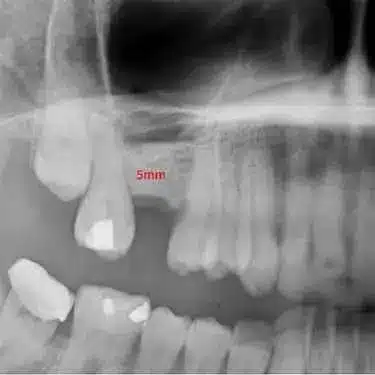

Durante esta valoración inicial, realizamos un escáner 3D o TAC dental de alta precisión que nos permite observar en detalle la cantidad y calidad del hueso disponible.

Esta imagen tridimensional nos ayuda a planificar el injerto con total seguridad, definiendo el volumen necesario y localizando estructuras anatómicas importantes como el nervio dentario o el seno maxilar.

Mediante revisiones clínicas y nuevas pruebas de imagen, confirmamos que la regeneración ósea avanza correctamente antes de programar la colocación del implante. Así garantizamos un resultado predecible, seguro y duradero.